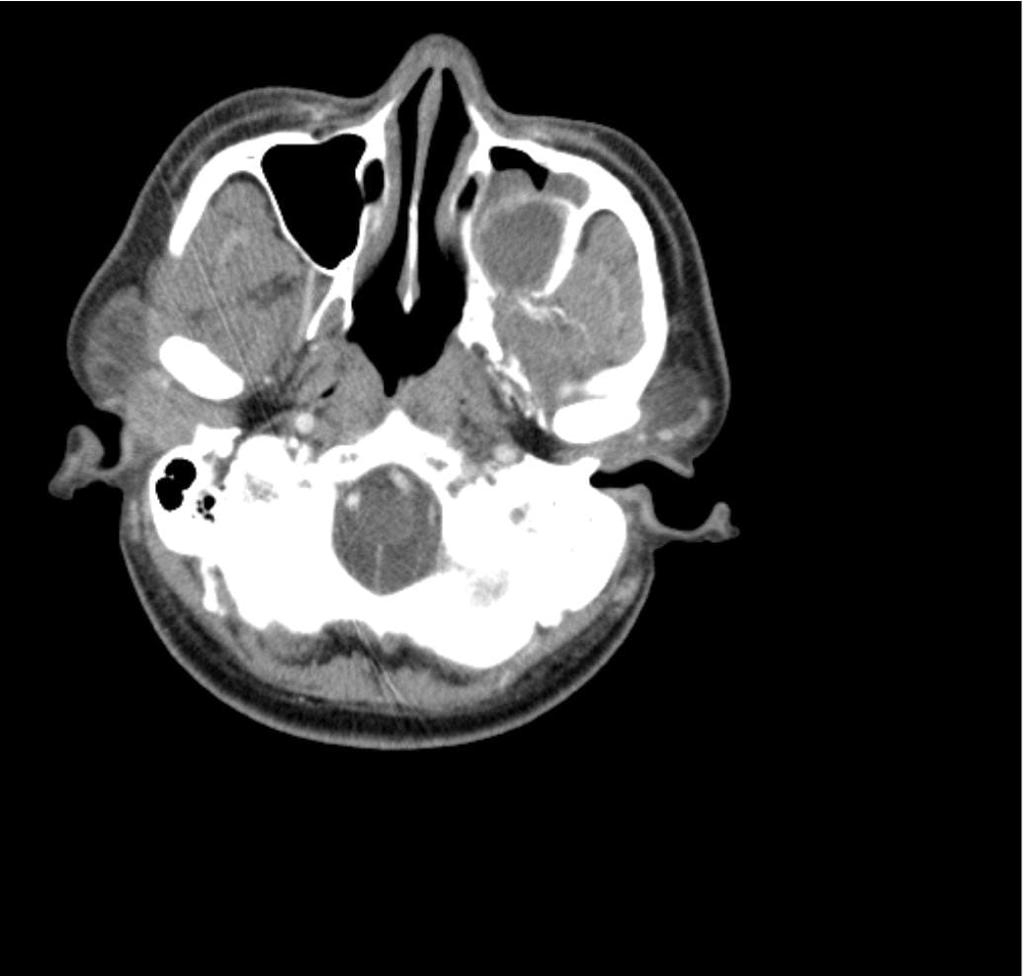

This is the case of a 25-year-old female, a resident of Nalgonda, and a homemaker, who presented to the outpatient department three days ago with chief complaints of  - Generalised body pains since 9 days - Bilateral knee ankle, metacarpophalangeal joint pains since 9 days - Fever since 6 days  - Headache since 6 days  History of presenting Illness  The patient was apparently asymptomatic 9 days ago when she developed generalised body aches  which were sudden in onset, continuous, aggravated with the onset of fever and relieved on taking medication.  9 days ago, the patient also had joint pains which were present bilaterally in the knee joints, the metacarpophalangeal joints, and the ankle joints. The Joint pains were of dull character, sudden in onset, continuous,  did not cause any functional impairment, and aggravated on the onset of fever.  6 days ago , the patient developed a sudden onset, high-grade fever, associated with chills and r...